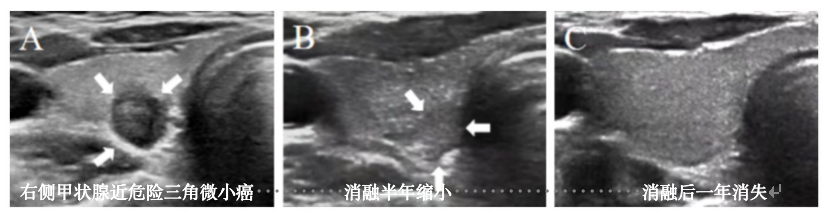

甲状腺危险三角微小癌消融后效果